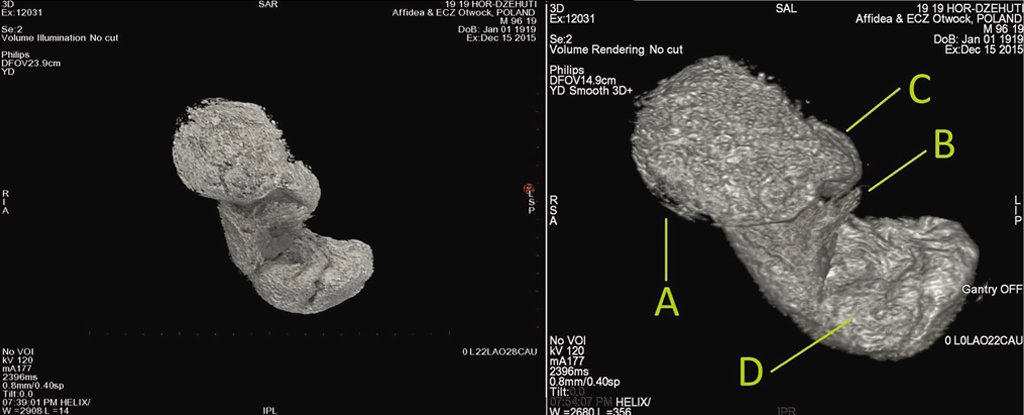

Molto famoso in tempi recenti è diventato anche il feto di sette mesi scoperto nel corpo di una mummia conservata al Museo di Varsavia (“Mysterious Lady”), ritenuta in passato il sacerdote di Horus Hor-Djehuty dalle iscrizioni sul sarcofago che la conteneva, ma non sappiamo ad oggi se la morte della mamma sia stata dovuta alla gravidanza.